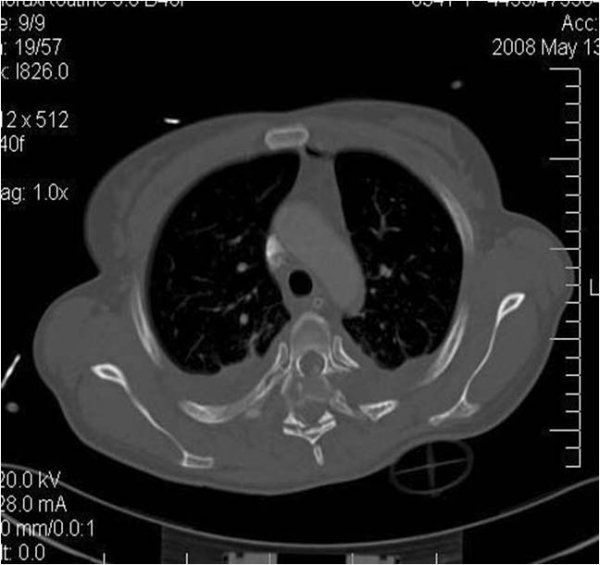

Radyolojik Görüntüler